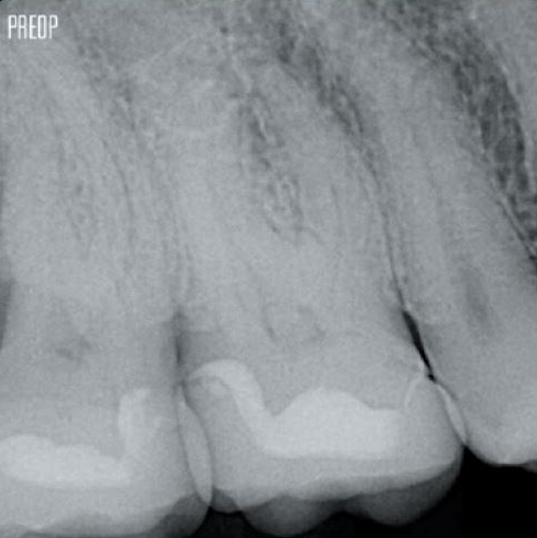

Retaining dentin serves as the critical base for a quality restoration following root canal treatment. The more dentin preserved during an endodontic treatment, the more options there will be to perform a successful, durable restoration.1

Successful root canal treatment starts with adequate access to the pulp chamber. The ideal procedure provides access to root canal orifices with minimal loss of dentin.

A Conservative Endodontic Cavity (CEC) is the recommended with the TruNatomy® system.

The union of the file geometry, regressive tapers and the slim, highly-flexible wire enables efficient root canal treatment while removing only dentin where clinically needed.1

More dentin preserved. Appropiate shaping, irrigation, and obturation ensured.

Photos courtesy of Dr. Ahmed Salman